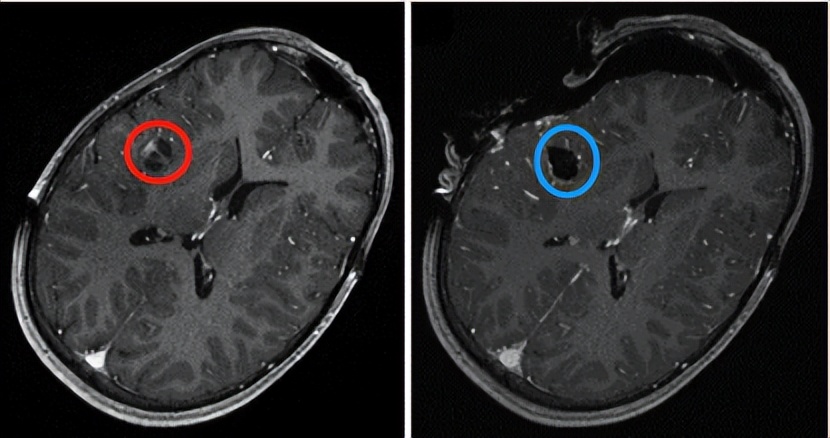

世界小儿神经外科学会前主席、德国INI国际神经学研究所小儿神经外科主席Concezio Di Rocco教授曾在其研究论文《Pediatric intracranial primary anaplastic ganglioglioma》通过对8年间(2007-2014)对16岁以下患者(范围0.8-15岁)进行了82次神经外科手术结果发现,MRI在儿童中的应用证明是安全的。它在增加肿瘤切除范围方面最有效,特别是对于低级别胶质瘤和颅咽管瘤患者。

在受右侧岛叶神经胶质瘤影响的11岁儿童中获得的MR图像。左:术前MR图像。右图:术中iMRI图像显示全切病变。来自Di Rocco教授公开发布的手术案例